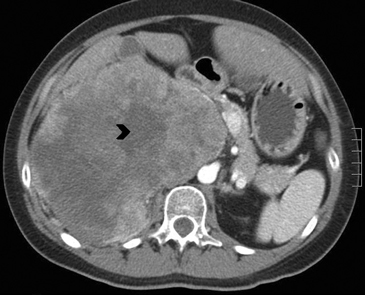

En TC sin contraste por lo general se observa una masa heterogénea, especialmente en caso de lesiones de mayor tamaño por la presencia de necrosis. Entre un 19 a 33% de los casos se identifican calcificaciones. Luego de la administración de contraste su refuerzo es heterogéneo y su patrón de lavado es consistente con una enfermedad maligna (Figura 22).

Los sitios más habituales de metástasis son hígado, pulmón, además de la invasión de las estructuras vasculares adyacentes, especialmente de la vena cava inferior, hallazgo que constituye una consideración fundamental al momento de planificar el abordaje quirúrgico (Figura 23 a y b).